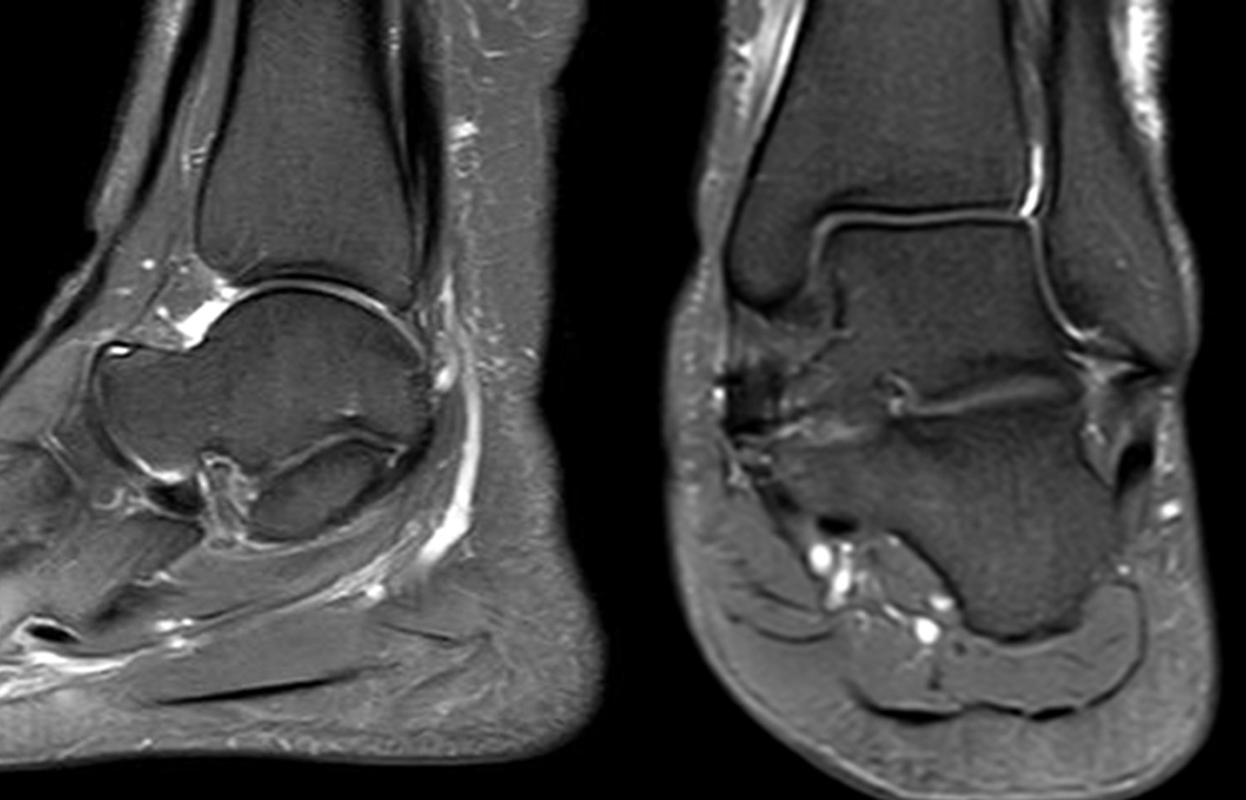

Die Abbildungen 4.2.a bis d zeigen den typischen Aspekt einer talacalcanearen Coalitio. Es besteht nur eine linksseitige, symptomatische Coalitio talocalcaneare (4.2.a und c); das 35 Tage zuvor angefertigte MRT zeigt keine auffälligen Signalveränderungen (4.2.b und d).

Abbildung 4.3. zeigt die Ursache für rechtsseitige Sprunggelenksbeschwerden bei einem Patienten mit talocalcanearen Coalitionen: nur die osteochondrale Läsion an der distalen rechten Tibia ist die Ursache des Schmerzes. Die bilateralen talocalcanearen Coalitionen sind asymptomatisch.